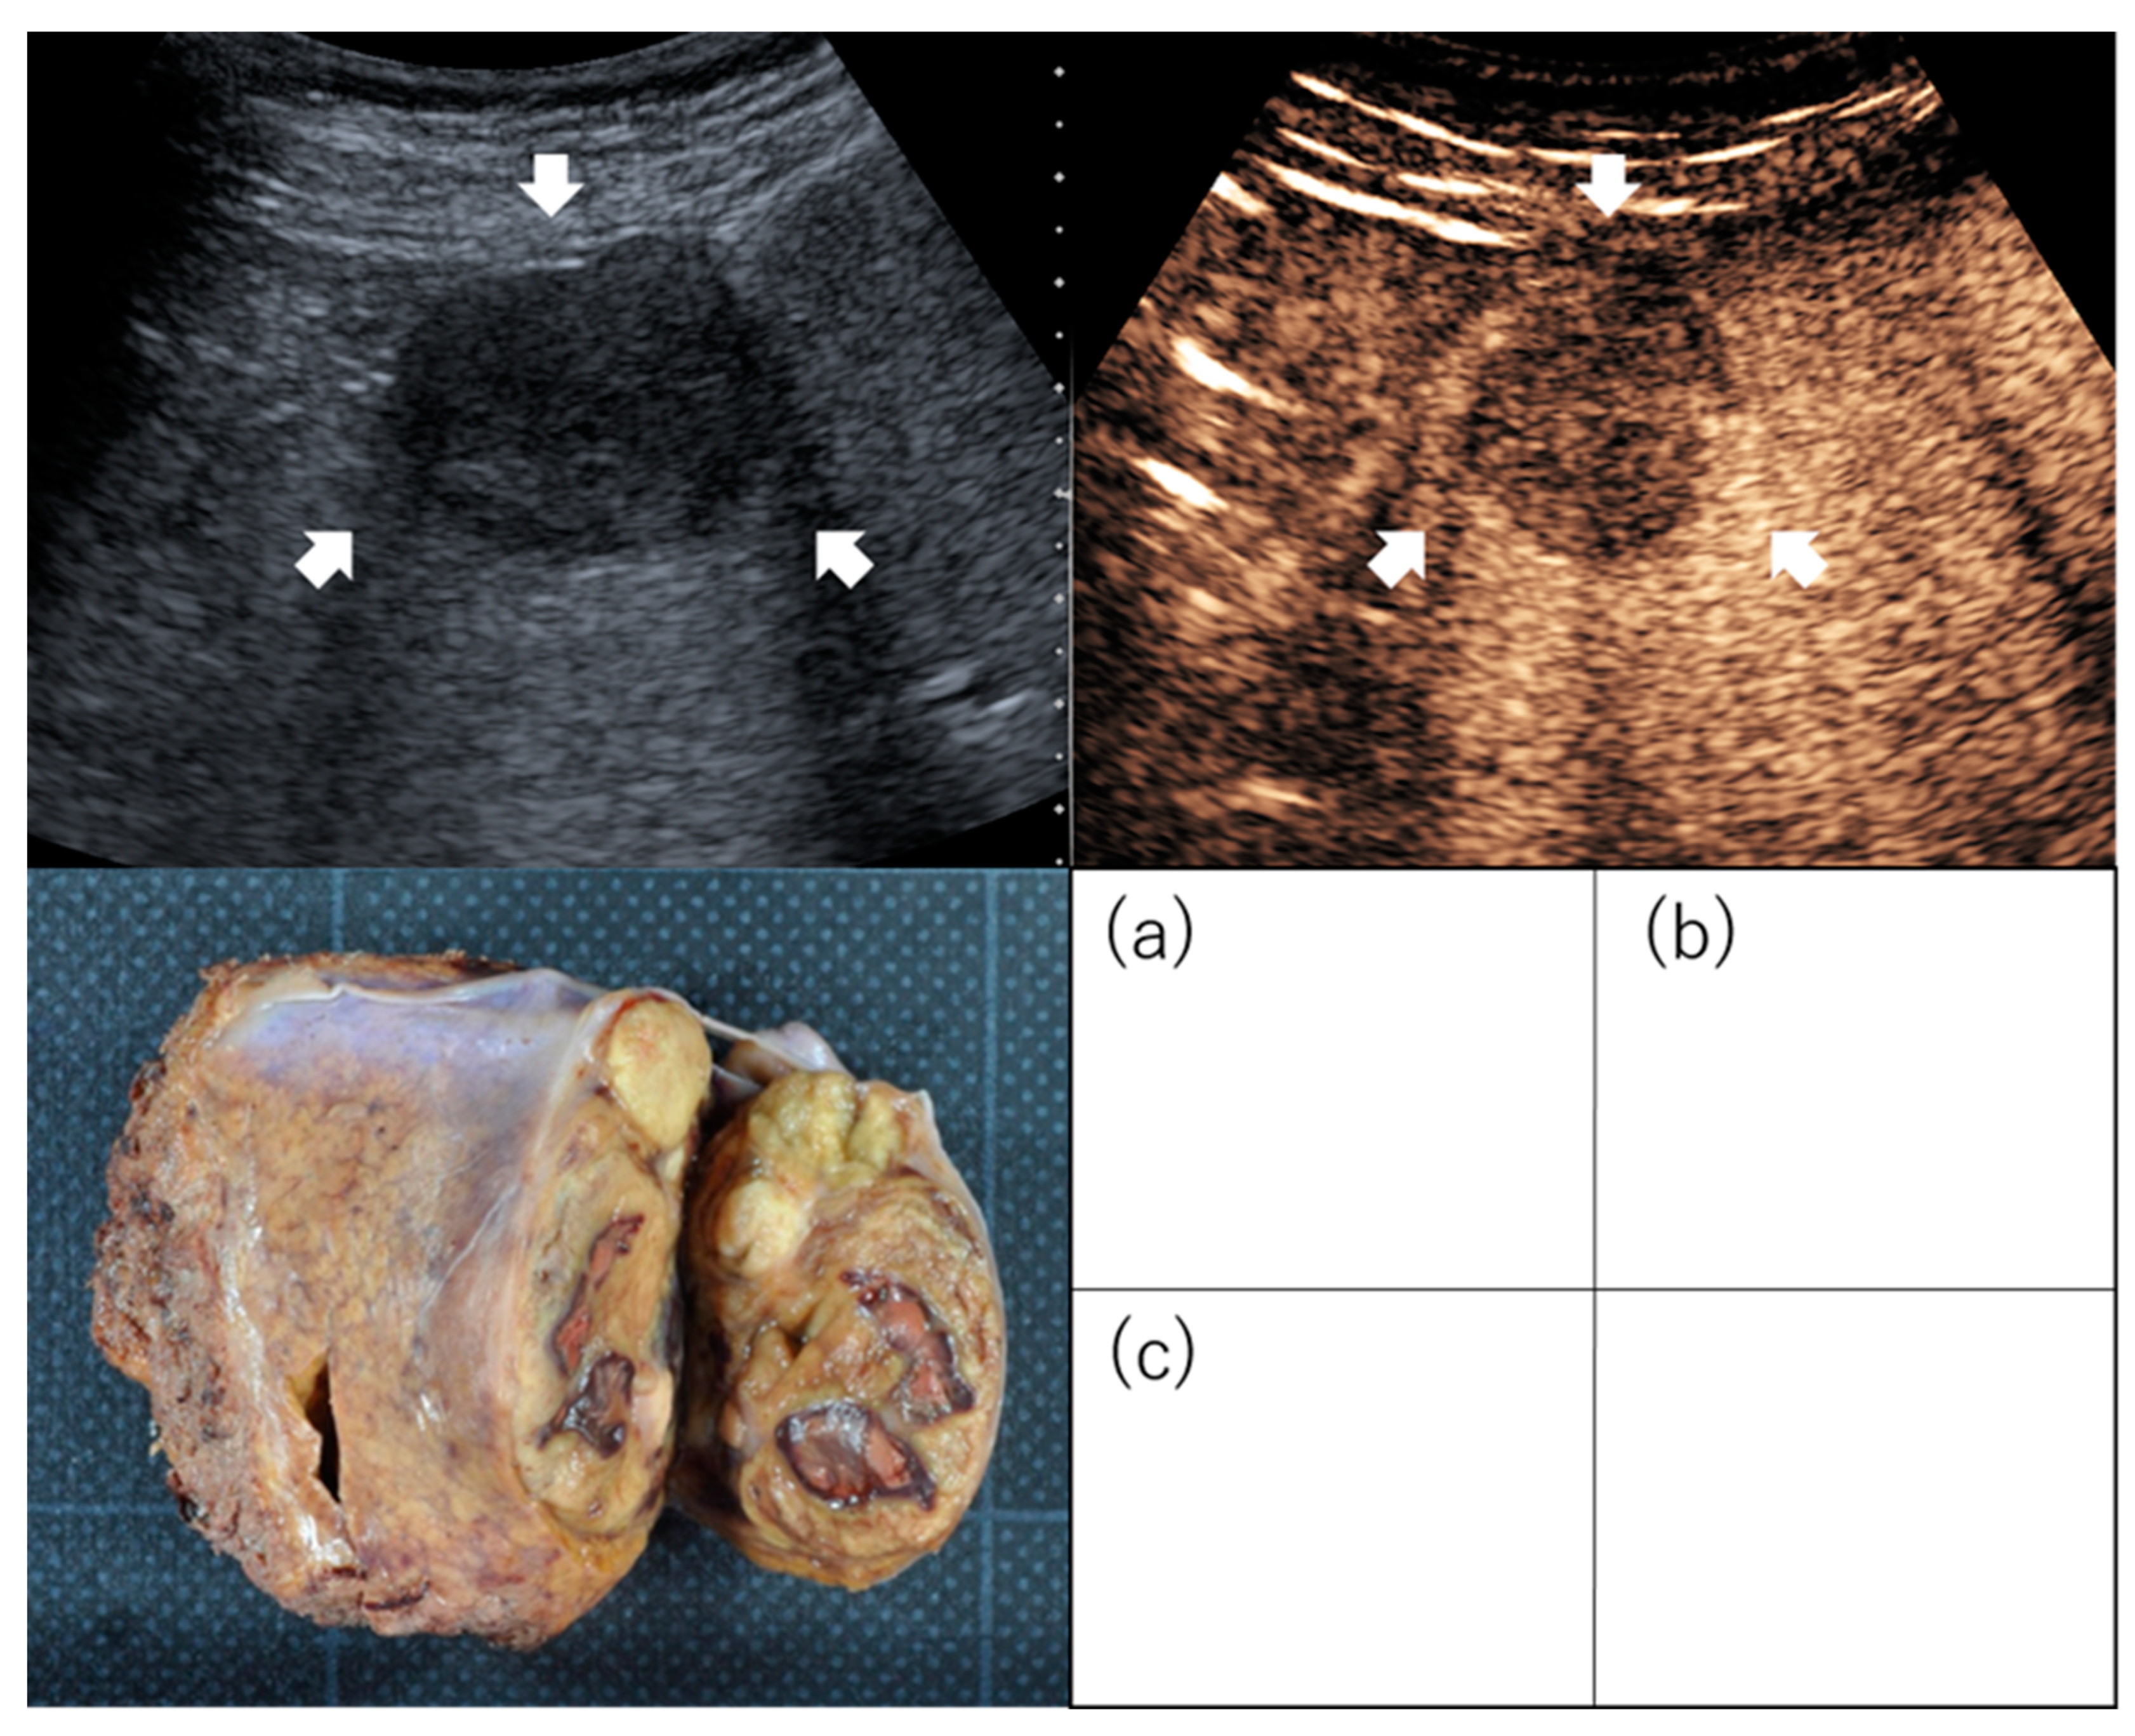

2.1. Gross Classification

- Hatanaka, K.; Chung, H.; Kudo, M.; Haji, S.; Minami, Y.; Maekawa, K.; Hayaishi, S.; Nagai, T.; Takita, M.; Kudo, K.; et al. Usefulness of the post-vascular phase of contrast-enhanced ultrasonography with sonazoid in the evaluation of gross types of hepatocellular carcinoma. Oncology 2010, 78 (Suppl. S1), 53–59. [Google Scholar] [CrossRef]